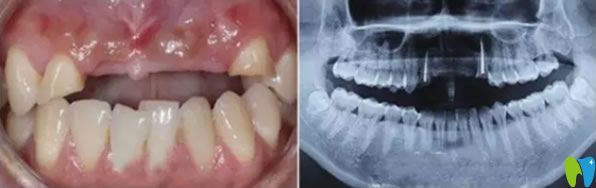

一次意外導(dǎo)致老公門牙缺失,在一家小診所做的烤瓷牙,這幾年用著還可以,但是前幾天發(fā)現(xiàn)牙齦萎縮很嚴(yán)重 ,明顯一個(gè)坑。三十出頭小伙子看著像四十多歲大叔,這可怎么辦?網(wǎng)上說牙齒缺失可以通過種植牙來修復(fù),我們也不知道有沒有年齡限制,老公都30多歲了還能做種植牙?成都瑞爾口腔在我們這的口碑挺不錯(cuò)的,我就陪老公來咨詢。

來院后面診的是郝亦工醫(yī)生,詳細(xì)檢查后,說老公的門牙可以通過牙齒種植來修復(fù),同時(shí)也能改善牙齦萎縮的現(xiàn)狀。郝主任說種植牙沒有年齡限制,只要身體無疾病,都可以種植。

郝醫(yī)生通過醫(yī)學(xué)種植技術(shù),根據(jù)老公牙齒狀況設(shè)計(jì)種植方案。他將種植體與人體兼容性高的鈦金屬精準(zhǔn)植入缺牙區(qū)的牙槽骨內(nèi),等三個(gè)月后,人工牙和牙槽骨緊密結(jié)合,再做烤瓷牙、全瓷牙冠。郝醫(yī)生植入牙根手術(shù)完成后,老公從手術(shù)室出來牙齦看著就沒有之前那么憋了,飽滿了許多。